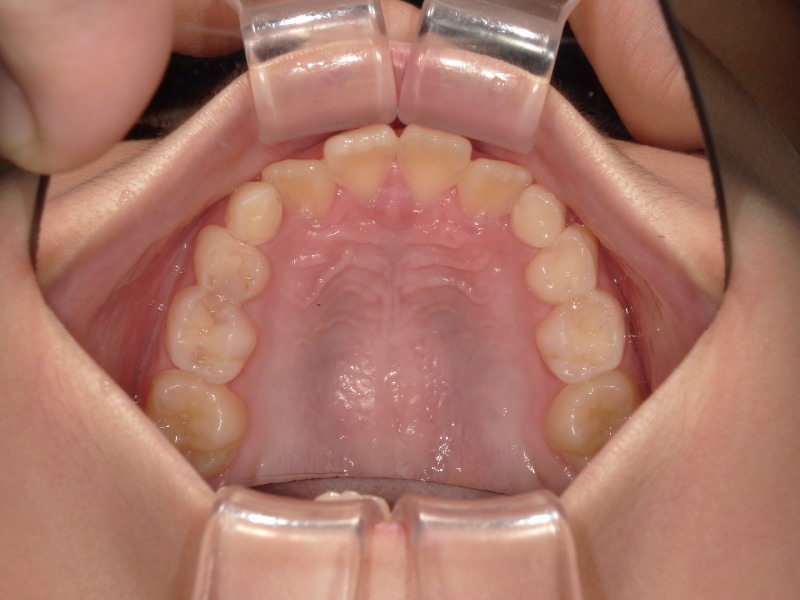

治療前 / 現在

現在

装置セットから外して数ヶ月後の写真です。

もう3番目の歯は綺麗に並ぶので全ての装置を外しました。

(アクティビティー終了しているため、マウスピースのに使用しています)